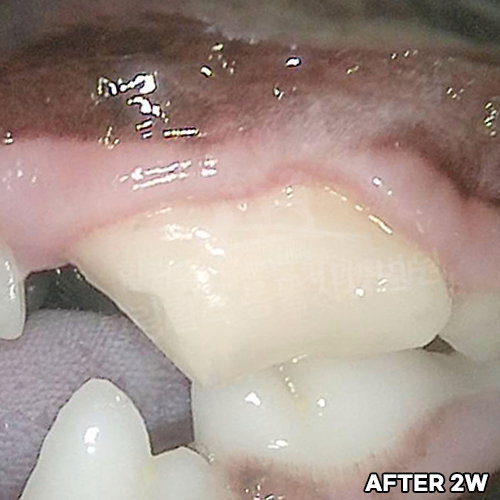

[강아지 치아파절 치료 후 4년 경과모습]

샘플